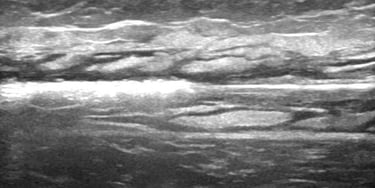

Our service offers a highly experienced Vascular Sonographer with the latest portable ultrasound technology to enhance your consultation sessions. With exceptional time management skills and a compassionate nature our Sonographer is well-equipped to provide valuable support and convenience to you and your patients.

We can accomodate your in-house interventional procedures for varicose veins using Endovascular Laser Therapy, Radiofrequency Ablation, Glue, Venoseal and Sclerotherapy. With over 10 years of procedural ultrasound experience alongside multiple surgeons across Perth, we have the experience to you with top quality.